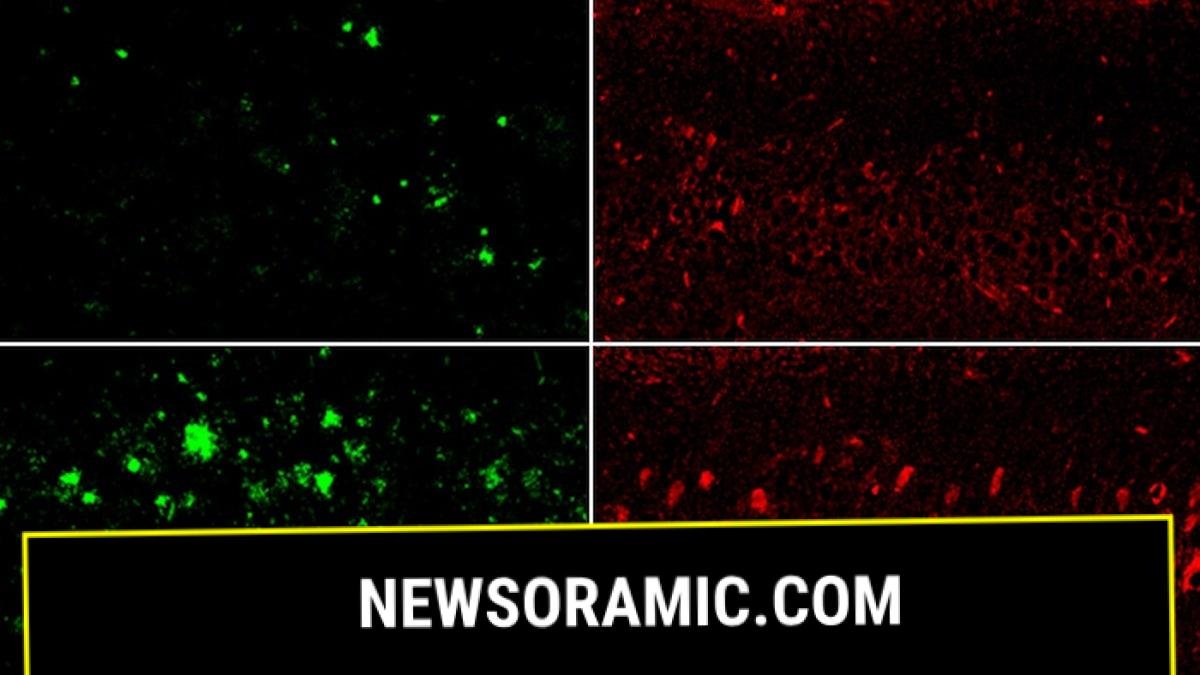

In a mouse model of Alzheimer’s disease, lithium deficiency, right, dramatically increased amyloid beta deposits in the brain compared with mice that had normal physiological levels of lithium, left. Bottom row: The same was true for the Alzheimer’s neurofibrillary tangle protein tau. (Yankner Lab)

As toxic amyloid plaques build up in the brain — a hallmark of Alzheimer’s — they begin to attach to lithium, keeping it from performing its protective functions.

When the mice were fed a “lithium-restricted diet,” their brains’ lithium levels decreased, causing accelerated aging, formation of amyloid-beta plaques, greater inflammation, memory loss and cognitive decline.